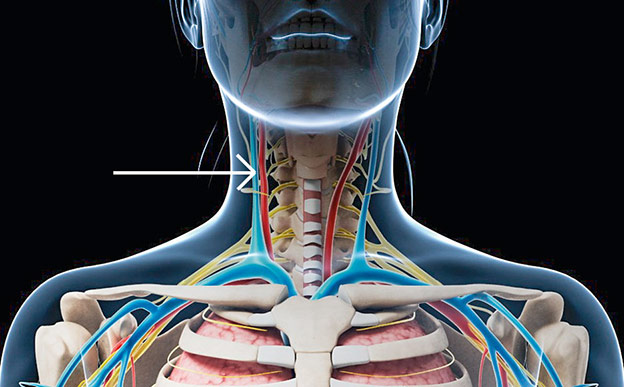

Las amígdalas

En los años setenta se extendió la práctica de extirpar las amígdalas ante cualquier síntoma, aun cuando no estuviera relacionado con una infección en la garganta. Se creía que, además de no servir para nada, podían potenciar ciertas patologías. Hoy se sabe que este tejido linfático es una primera defensa que, ante todo en la infancia, activa la respuesta inmune. Y un reciente estudio con más de un millón de niños revela que quitar las amígdalas triplica el riesgo de asma, bronquitis y neumonía. Eso sí: en caso de infecciones severas repetidas, habrá que eliminarlas.